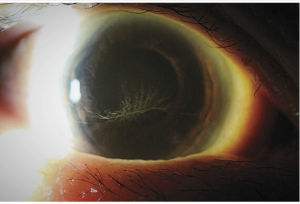

類型分布

KP有3種分布類型——一下方的三角形分布

二角膜瞳孔區分布

三角膜後瀰漫性分布